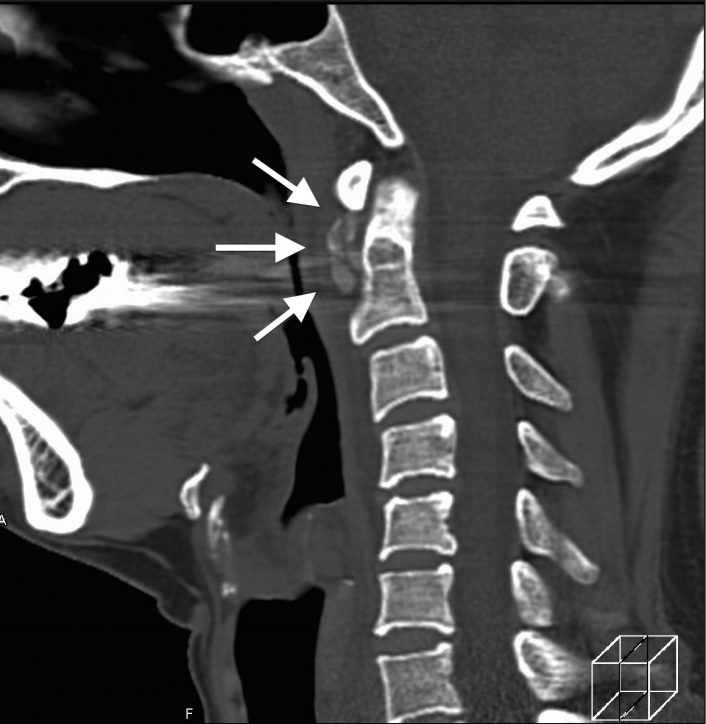

一位84岁的男性患者,因“急性颈痛、僵硬伴发热”就诊。查体:颈椎向各个方向活动受限,无明显神经病变体征。实验室检查:血沉及C反应蛋白偏高。颈椎CT平扫提示齿状突横韧带钙化(箭头所示),从而诊断为齿状突加冠综合征。给予洛索洛芬治疗一周后,上述症状完全缓解,而且炎性指标恢复正常。

患者女,76岁。无明显诱因下出现颈部疼痛、僵硬伴发热 3 d 入院 ,颈部疼痛呈间歇性,颈痛视觉模拟评分(VAS)为7分,体温37.7~38.8℃,无四肢疼痛麻木,无行走不稳,二便正常。既往无痛风、类风湿关节炎病史。入院体检:颈椎旋转明显受限,颈部肌肉僵硬,未查及明显神经或脊髓损伤体征。实验室检查:白细胞11.2×109/L,红细胞沉降率35.4 mm/h,超敏C反应蛋白14.7 mg/L,类风湿因子及降钙素原正常。颈椎CT平扫示齿状突后侧寰椎横韧带弧形钙化(左图箭头)和竖直线样钙化(右图箭头)。依据患者病史、体征及辅助检查,齿状突加冠综合征可基本诊断。入院后给予氯诺昔康 8 mg静脉滴注每日2次,地塞米松起始量10 mg静脉滴注每日1次,3日后改为5mg/d。连续治疗5 d后,患者入院时症状明显缓解,复查白细胞、红细胞沉降率、超敏C反应蛋白均恢复正常。随访半年,未有颈痛伴发热症状出现。